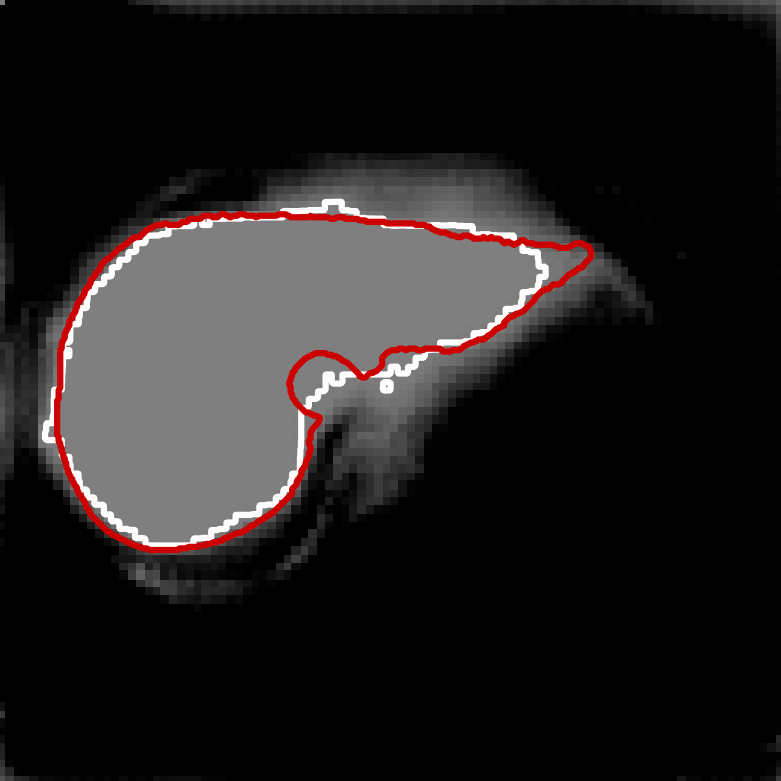

Figure 1 shows the results of the four individual segmenters. The grey level intensity reflects the probability map of foreground versus background. The white contour is the proposed segmentation boundary obtained by thresholding the probability map at 0.5. The red contour is the ground truth. 999The image for this example is slide 11 from the data of patient number 4 in the CHAOS dataset.

| U-net | Deepmedic |

|

|

| V-net | Dense V-networks |

|

|

In order to show the advantage of the ensemble, we chose a small, notoriously difficult, region to zoom on: vena cava superior (the blue rectangle in the U-Net plot in Figure 1). Figure 2 contains five plots of the segmented region. The product combiner was chosen for the ensemble. The ground truth is shaded in blue in the ensemble plot, and in red in the plots for the individual segmenters. The guessed segmentation is overlaid in transparent grey. The Dice score for the chosen area is shown under each plot. A Dice score of 1 indicates perfect segmentation while lower values indicate mismatch. As the results show, both visually and through the numbers, the ensemble segmentation is better than any of the individual ones.